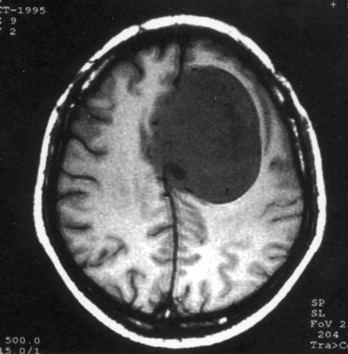

问题 病历摘要:??患者女性,37岁。大便时突起炸裂样头痛3小时,伴喷射样呕吐。既往体健。体检:T37.5℃,BP145/90mmHg,R20次/分,P85次/分。神志清楚,颅神经检查无异常,颈强直,克、布氏征(-),四肢肌力、肌张力正常,病理征(-)。 目前一般认为颅内动脉瘤形成的病因主要有哪些?提示:入院后?10小时行DSA检查,发现前交通动脉瘤